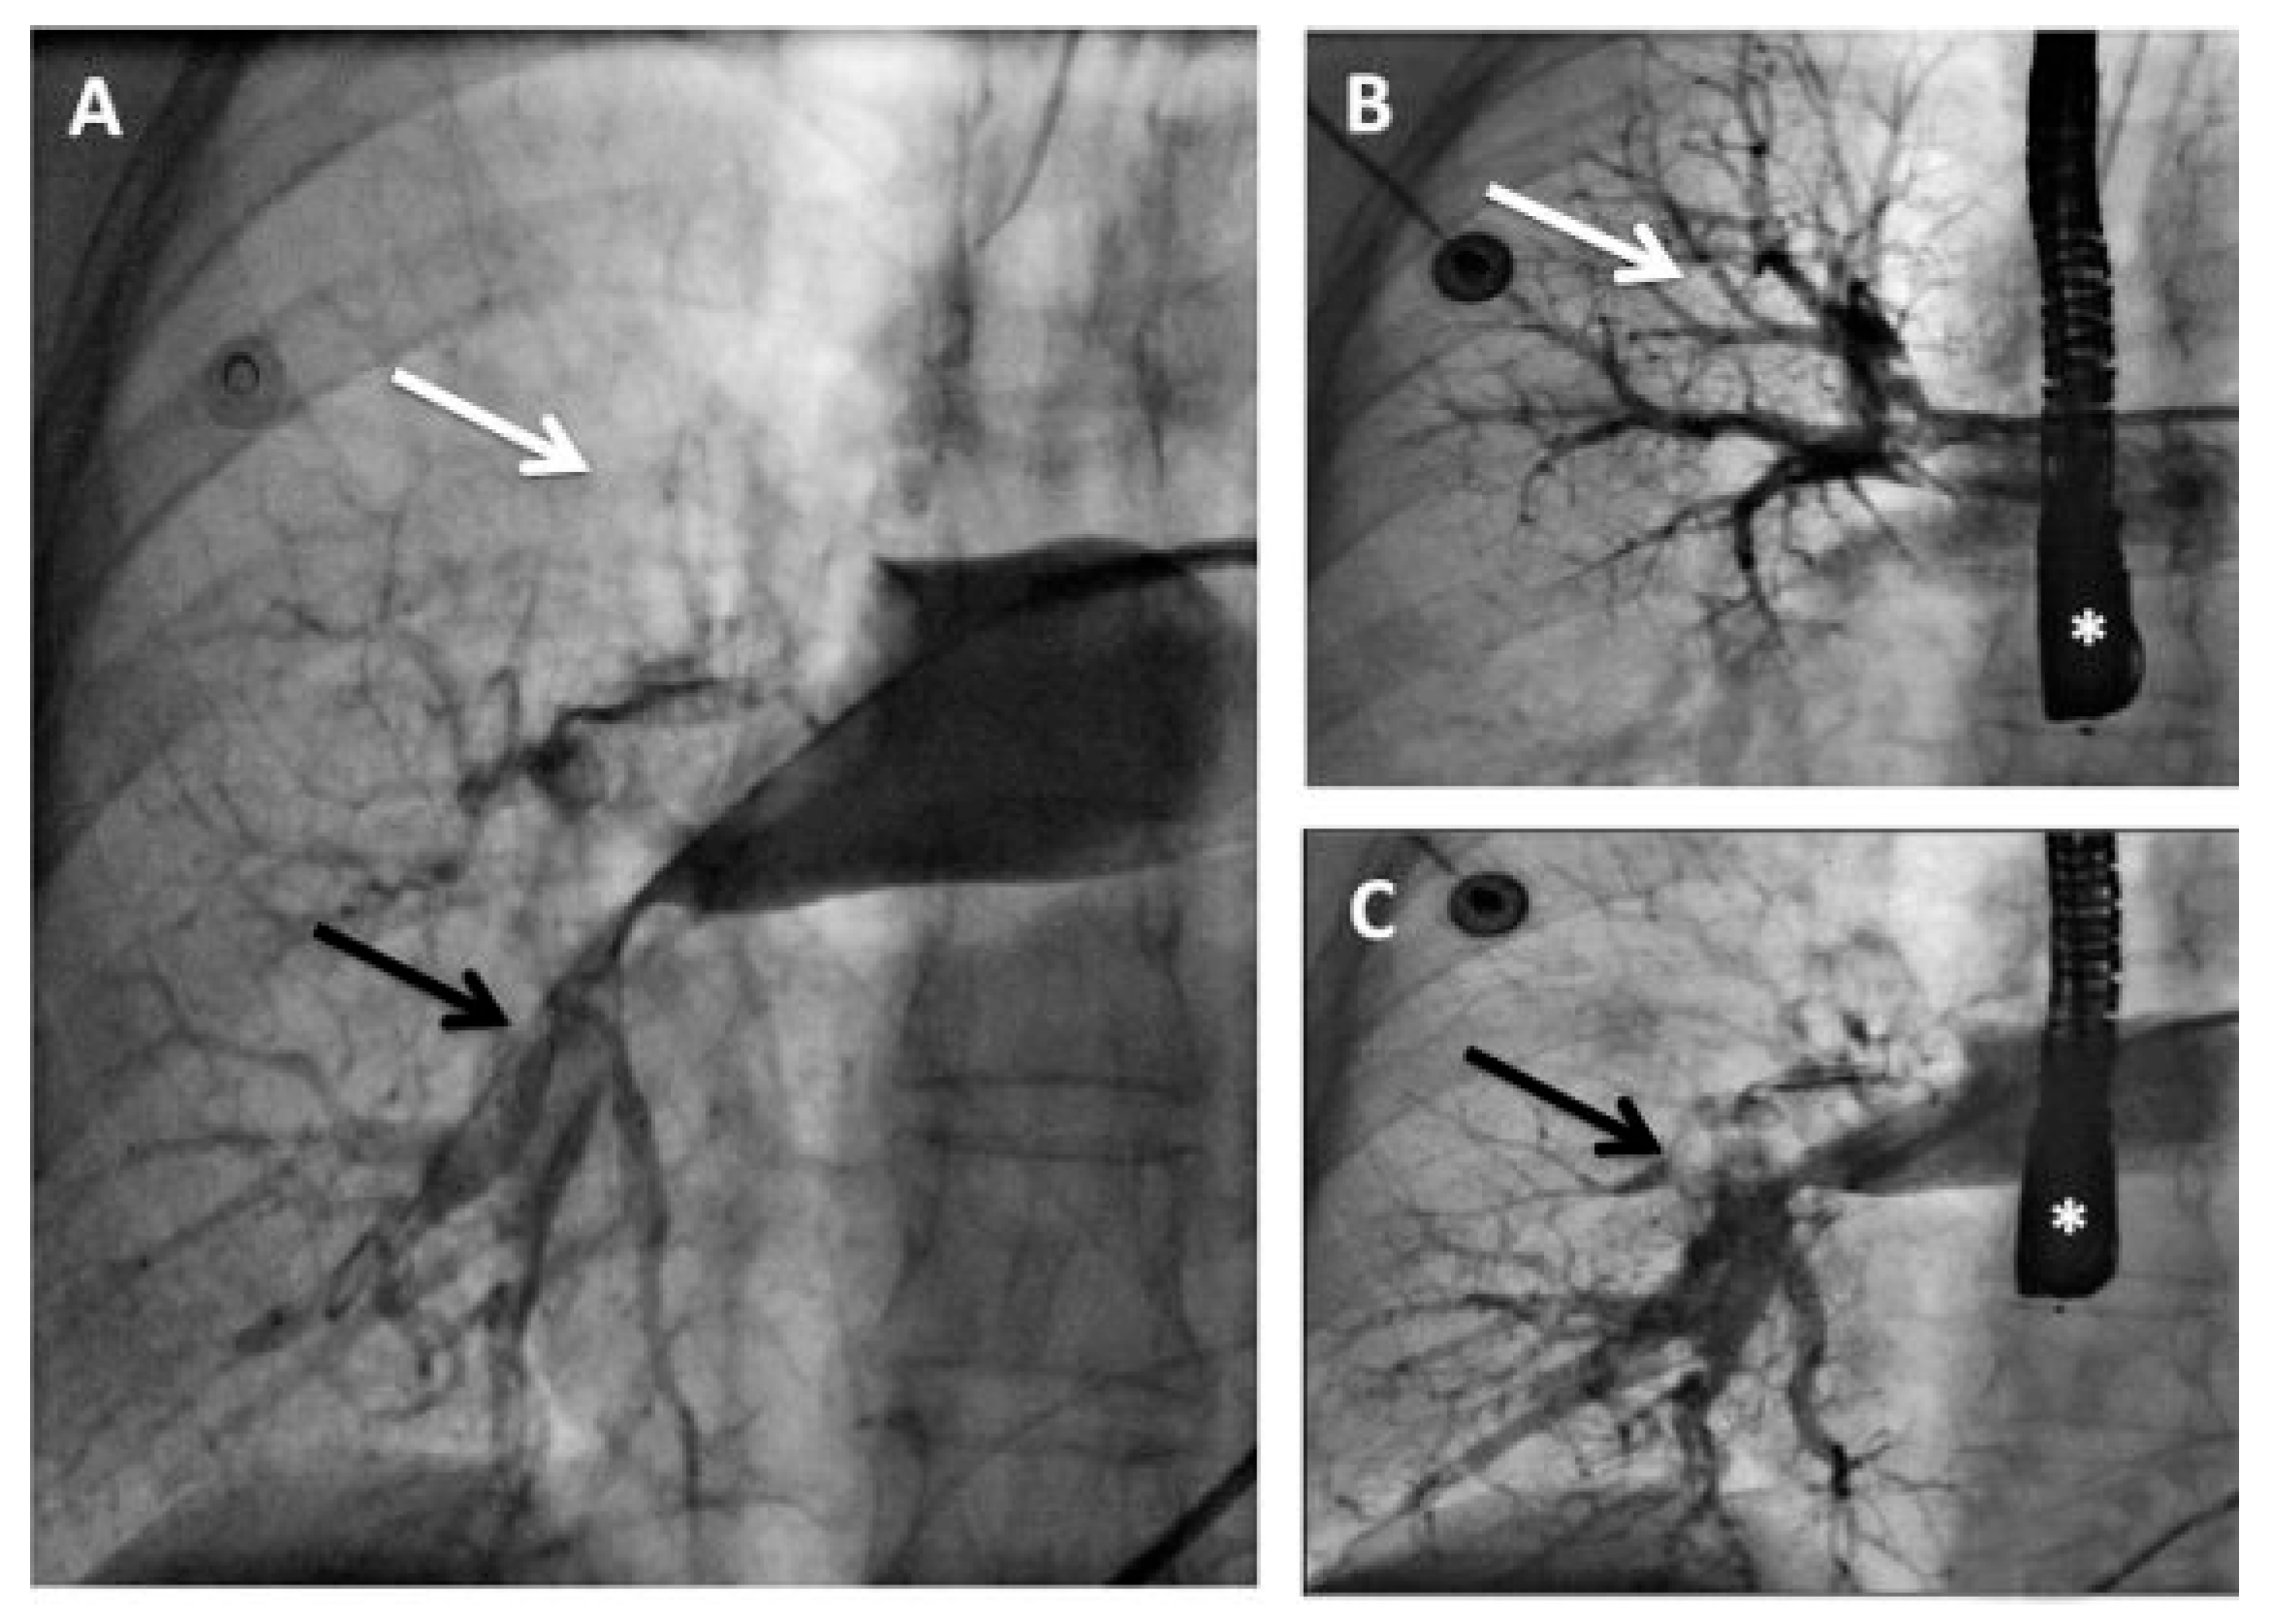

The intended strategy was to first perform rheolytic thrombectomy at the level of the IVC/RA and subsequently in the pulmonary arteries without administration of systemic or local fibrinolytics. However, the inferior cavography performed at the beginning of the procedure showed that the thrombus was not at the IVC/RA transition as suspected, but that it was lodged into the RA at the level of the fossa ovalis (Figure 1). Associating this imaging with the clinical presentation of a combined ischaemic stroke and massive PE, the presence of an IPDE was suspected. At that moment, the rheolytic thrombectomy was performed only at the pulmonary level and a trans-oesophageal echocardiography (TEE) was scheduled to confirm the presence of an IPDE.

Figure 1. Inferior vena cavography in anterior-posterior (AP) projection through an 8 F Multipurpose guiding catheter (black arrowhead) positioned in the inferior vena cava demonstrating a large right atrial thrombus (white arrows) at the level of the fossa ovalis. White arrowhead = right ventricle; black arrow = inferior vena cava.